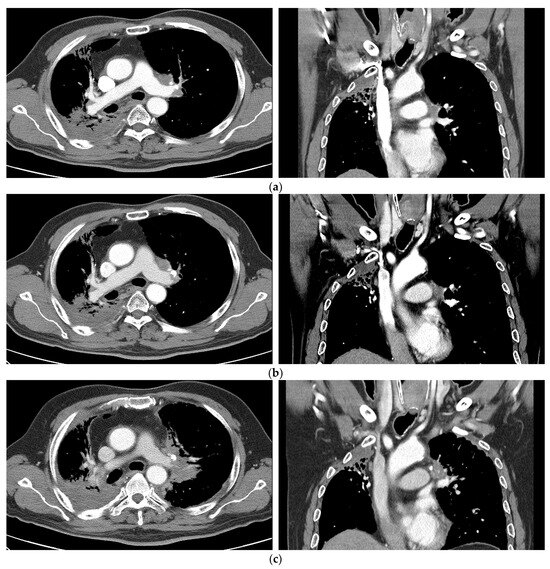

3.5. PD and a Case of Fatal Hemoptysis

| 7 | 62, M | 19.1 | Salvage s/p CCRT (interval 3.5 years) | Emphysema, PTE | Never | rcT0N2M0 | Lt prevascular, Lt hilar | SqCC | Chemotherapy | 67.4 | 55 Gy/10 fx | PD |

| 11 | 62, M | 35.3 | Salvage s/p CCRT | COPD | never | rcT2N0M0 | RML/RLL central | SqCC | Chemotherapy | 29.1 | 55 Gy/10 fx | PD |

| 15 | 58, M | 9.1 | Salvage | no | never | rcT4N0M0 | LLL | ADC | Chemotherapy | 42.2 | 50 Gy/10 fx | PD |